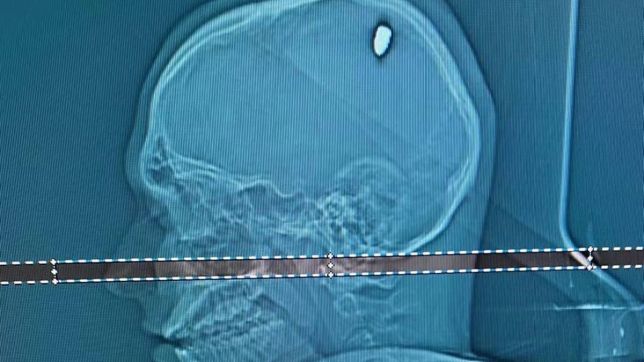

Um exame de tomografia mostrou que Mateus estava com uma bala alojada na cabeça. “Parte dela penetrou no cérebro. Isso causou compressão da região, e os movimentos involuntários do braço”, explica o neurocirurgião Flávio Falcometa.

“Por poucos milímetros, ela poderia causar um dano bem mais grave, como ficar com o braço paralisado ou metade do lado do corpo paralisado. Foi arriscado, bem arriscado para o paciente. A gente acredita que em 20, 30 dias, ele vai seguir com a vida normal dele”, completou o neurocirurgião.